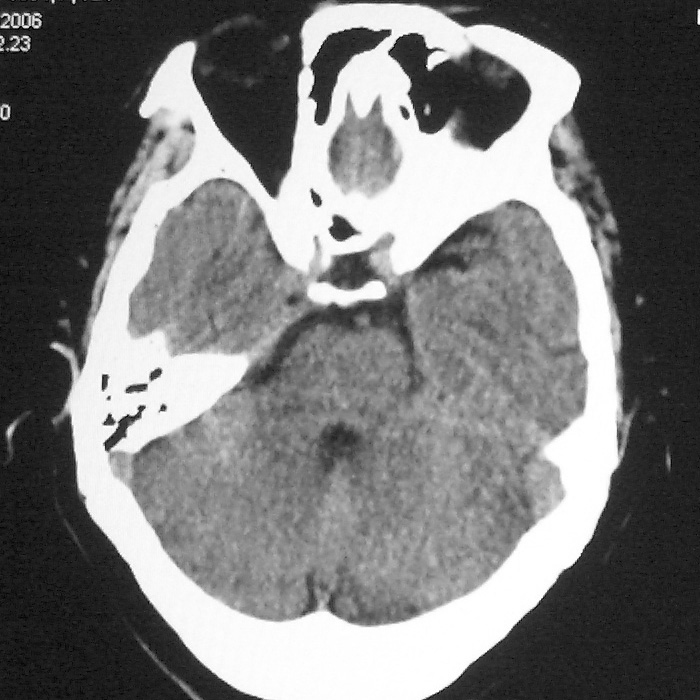

症状这么明显的话一般不会是单纯面神经麻痹引起的,最好做个mri,如果确实没有问题的话才能考虑面神经麻痹,毕竟这两种病的治疗和预后不一样,这个病人还有脑白质疏松。

双侧多发腔梗

1、右侧基底,左侧半卵圆中心腔梗。2脑萎缩。

双侧多发腔梗 脑萎缩